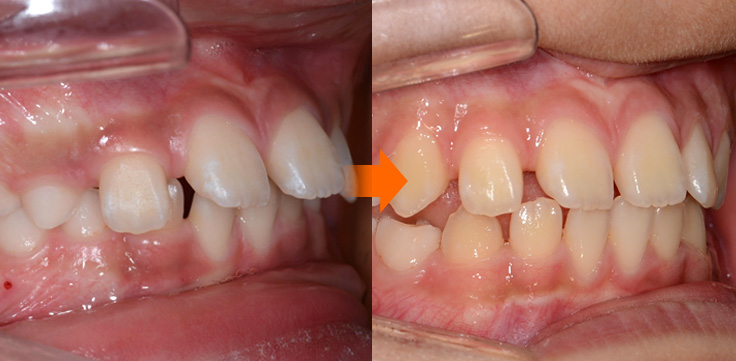

Anterior Cross bite

반대교합(주걱턱 예방)

주걱턱

주걱턱, 조기에 예방할 수 있습니다.

페이스마스크를 활용한 악정형 장치로 앞니 반대교합을 개선하고, 주걱턱을 미리 예방할 수 있습니다. 적절한 시기의 예방교정을 통해 자연스럽고 건강한 치열로 성장할 수 있도록 도와주었습니다.

• 주증상

전치부 반대교합

• 치료기간

약 6개월

• 부작용

치아표면의 탈회, 치은 부종, 치근흡수 등의 부작용이 있을 수 있습니다.